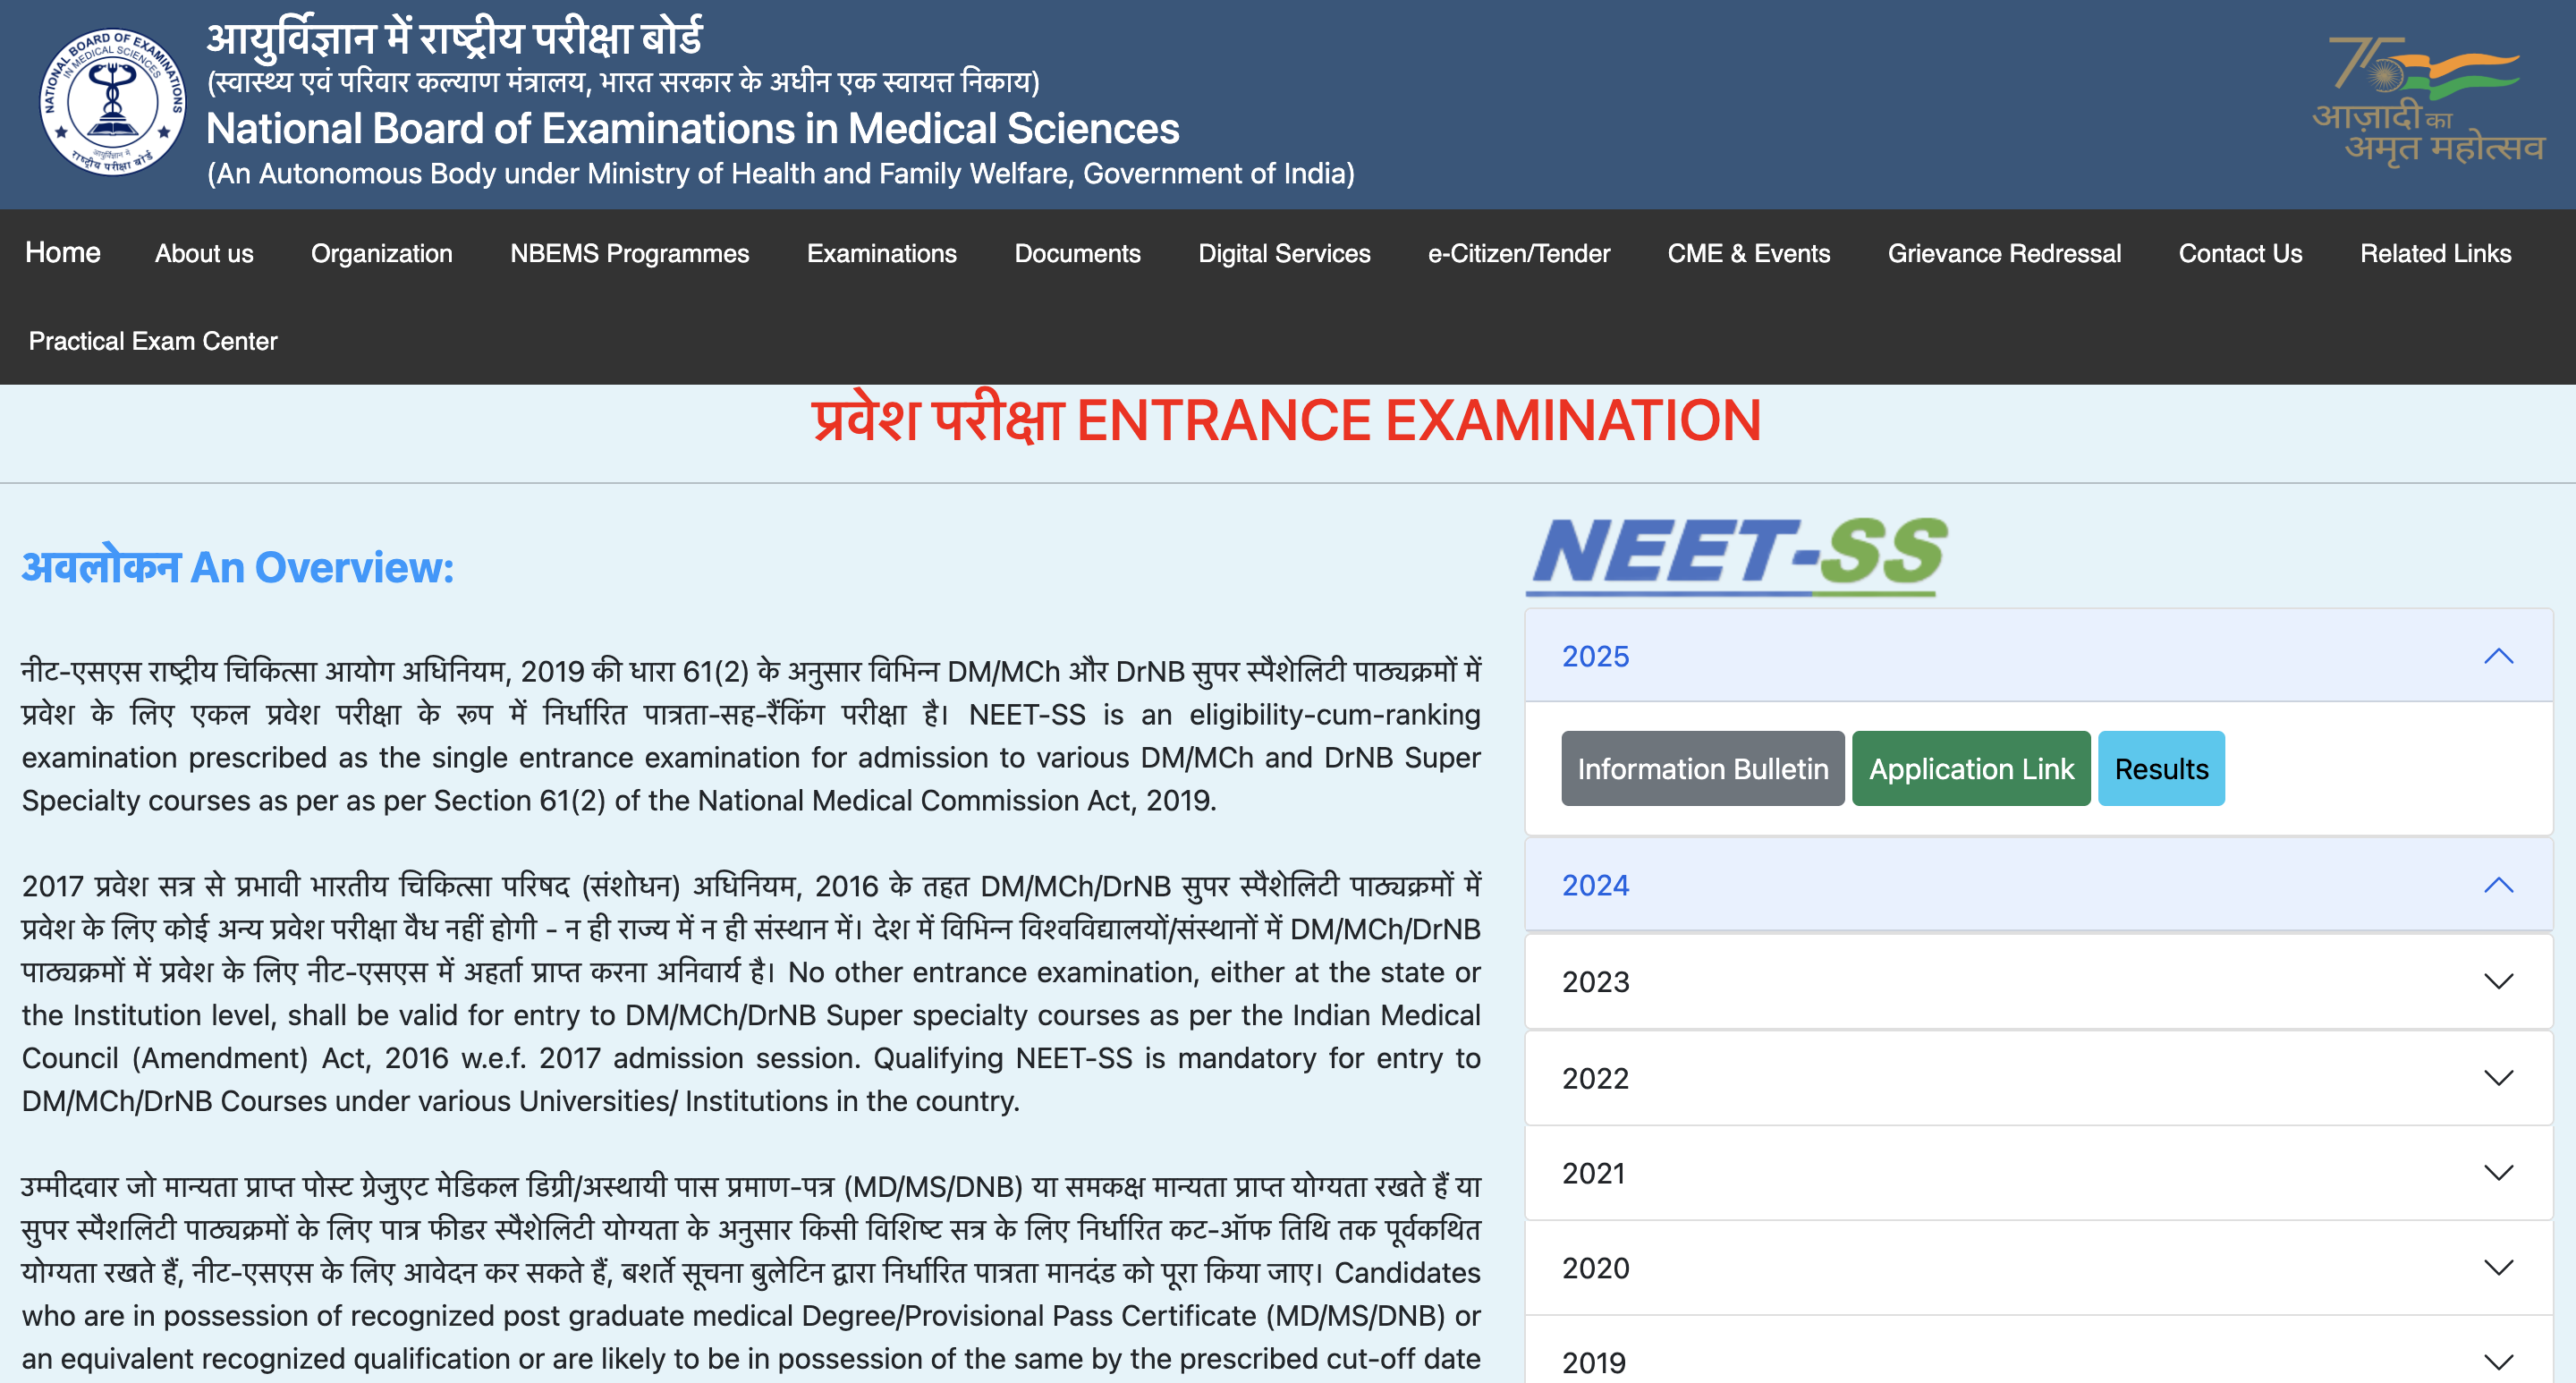

SC turns down plea to stay NEET counselling

NMC turns 5, with no patient appeals heard